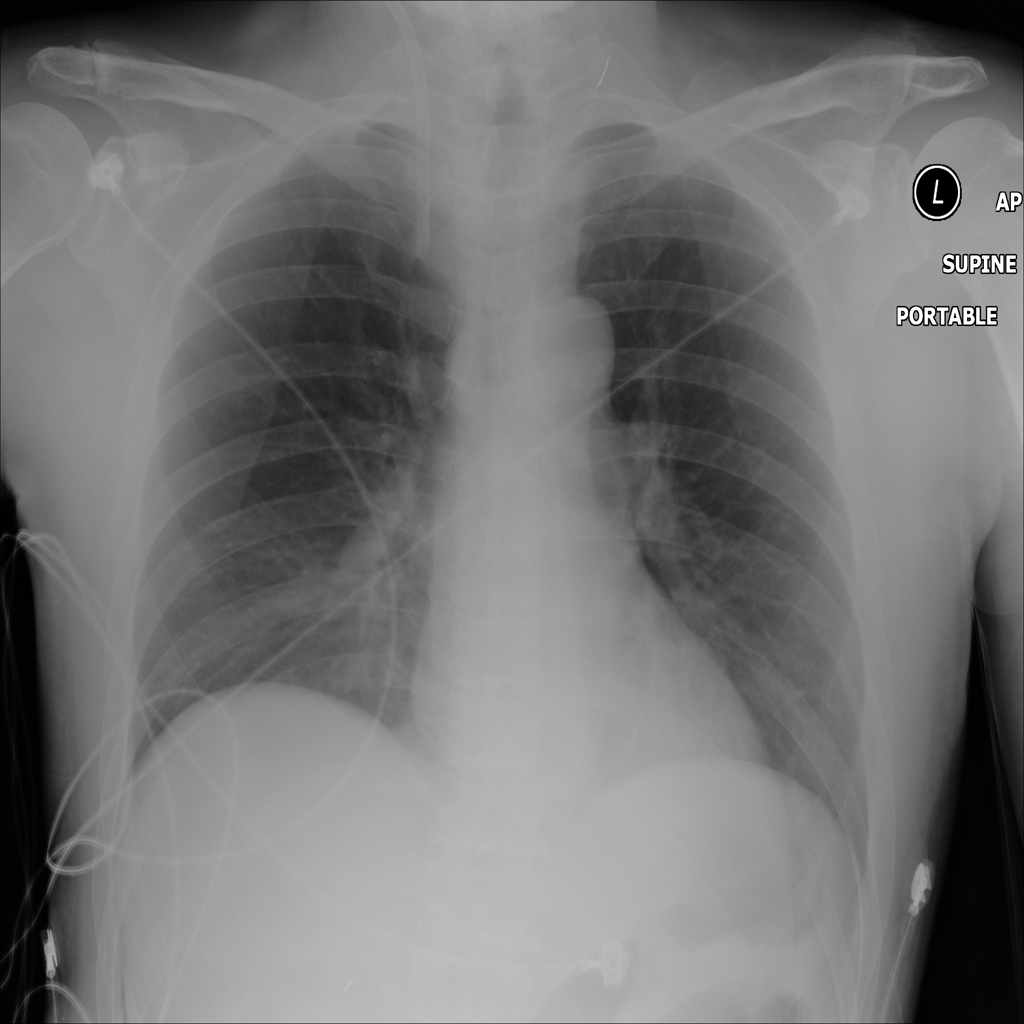

Showing up to 90 reference images for Pneumonia.

PAT-C0E5 · IMG-015Pneumonia

PAT-C0E5 · IMG-015

AP